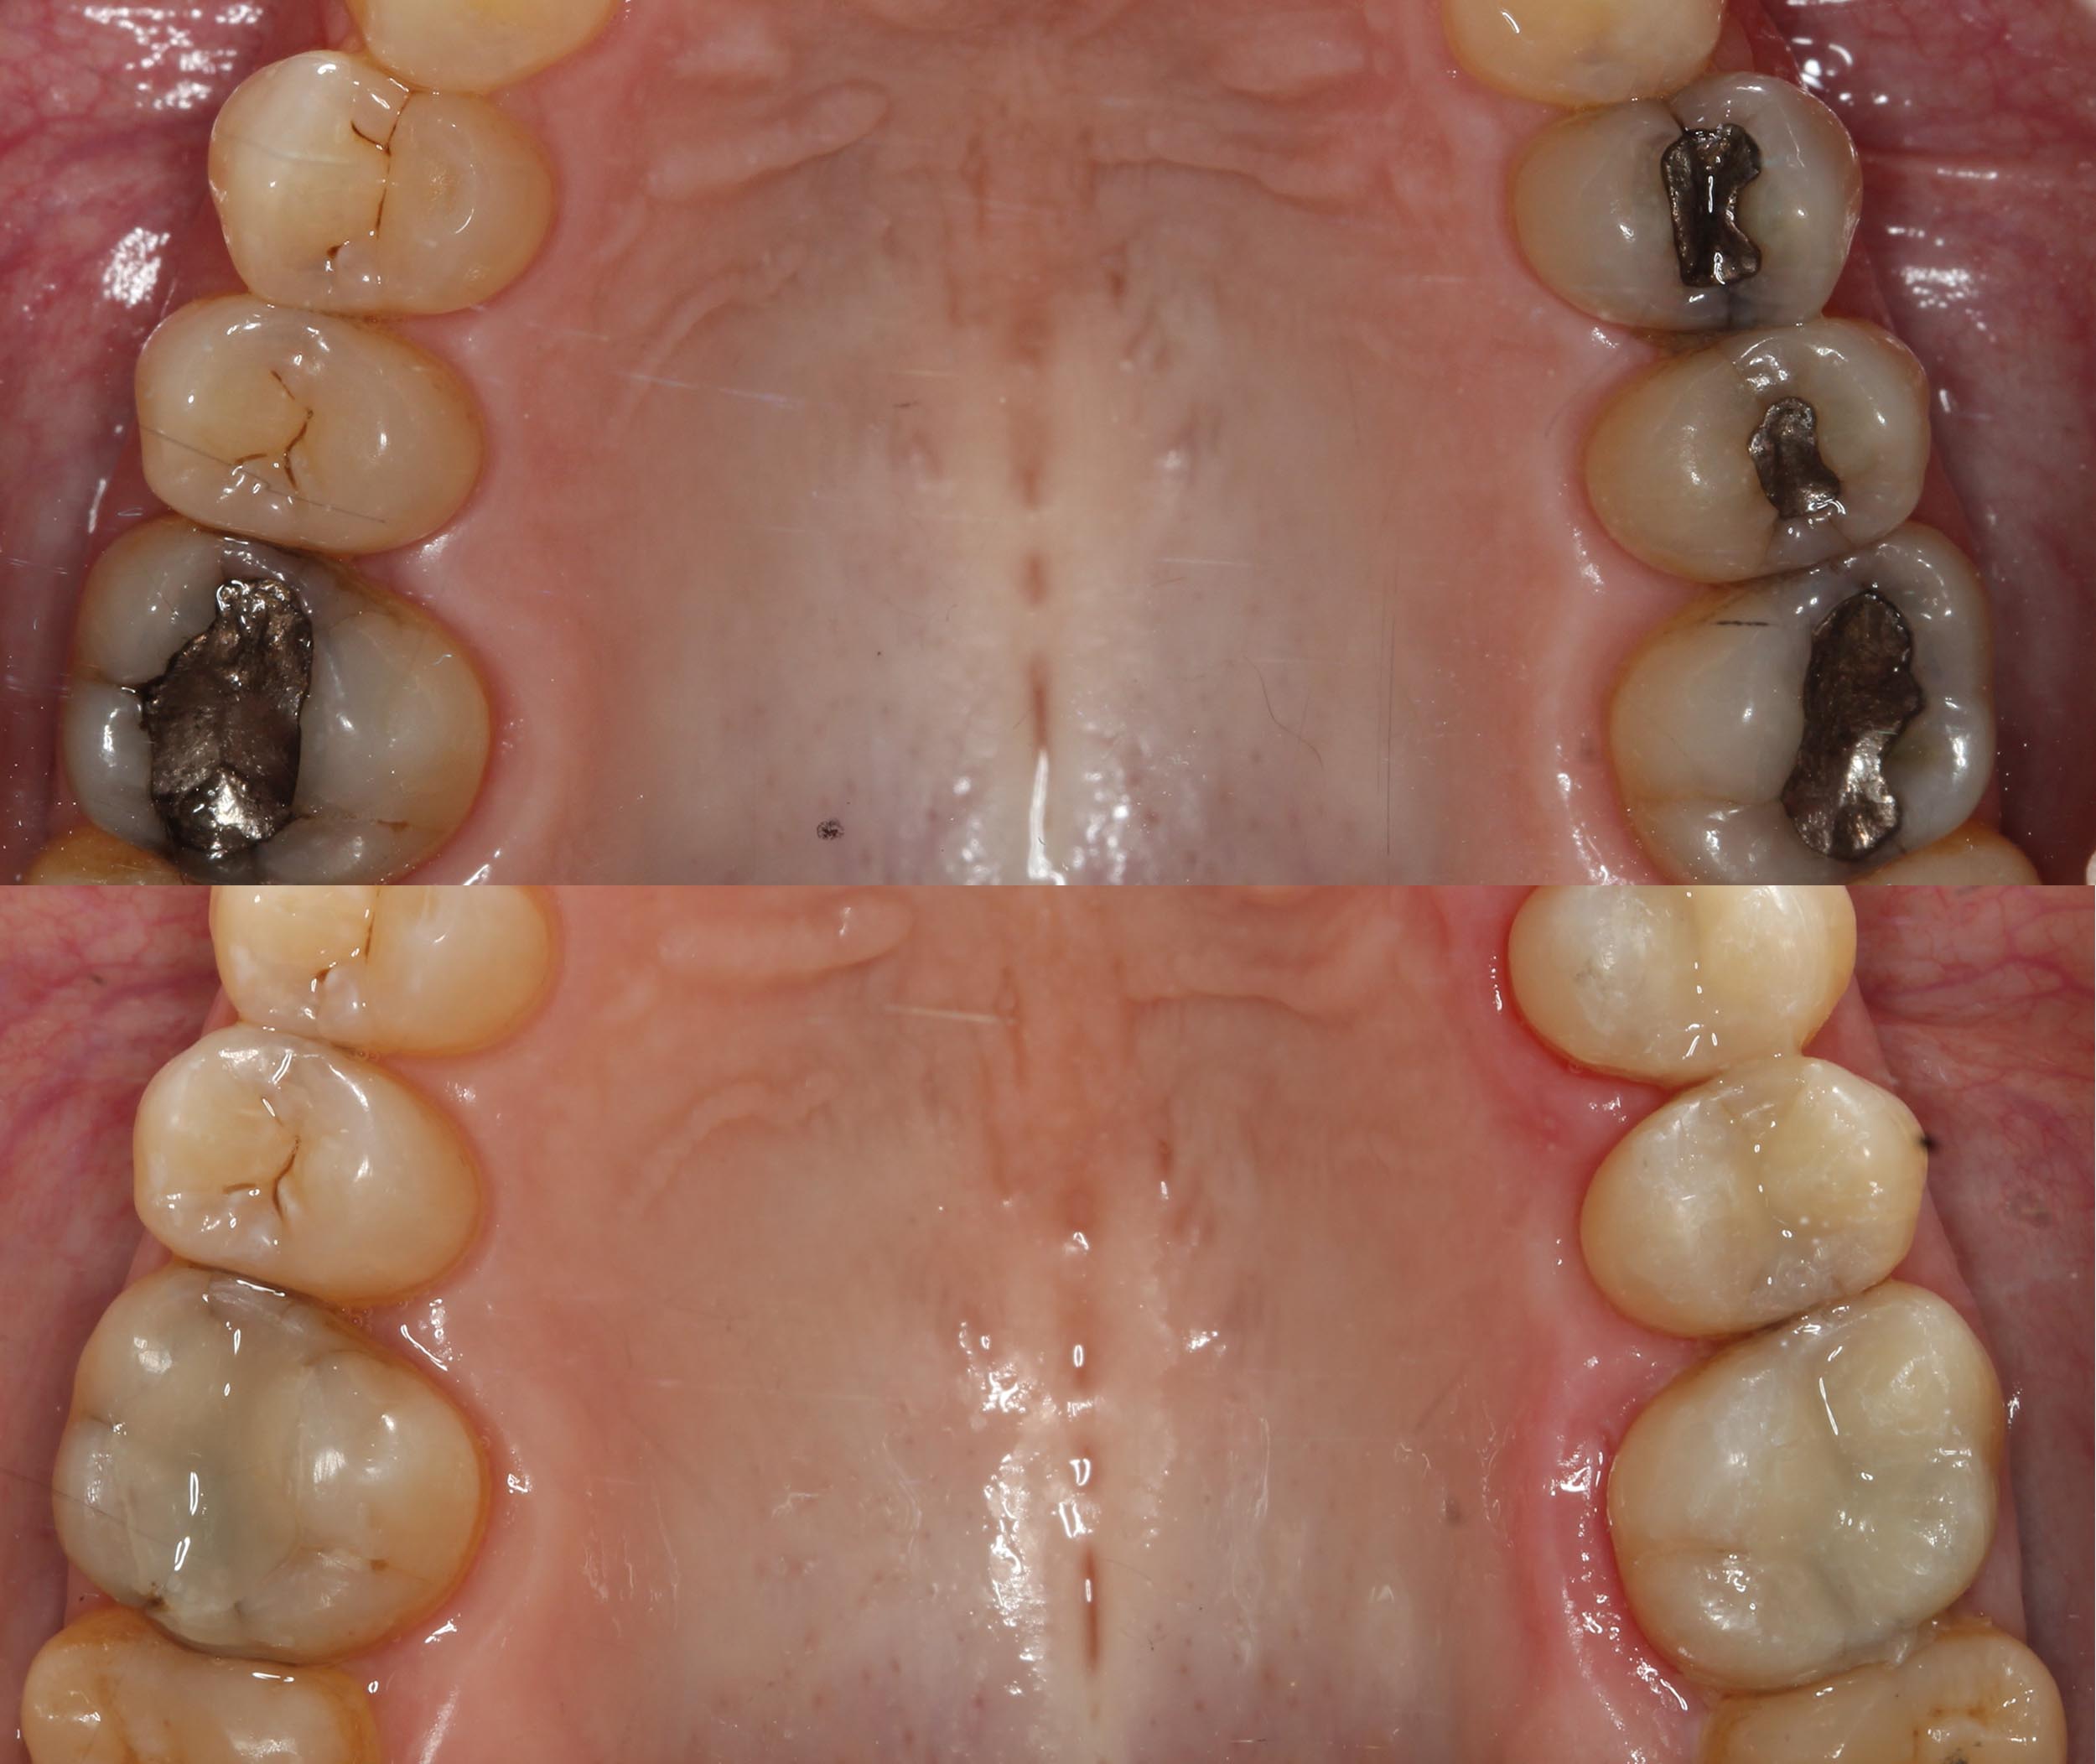

Las obturaciones de amalgama de plata, están formadas por alrededor de un 50% de mercurio , y el otro 50% es una aleación con otros metales como plata, cobre, estaño y zinc. Como explicamos en el post anterior, el mercurio es tóxico y sus vapores también, lo que puede representar un peligro para la salud. Éste, se absorbe y se retiene en órganos como cerebro, riñón, hígado, pulmón y tracto gastrointestinal.

Es por ello, que en Kimo aplicamos técnicas especiales para eliminar este tipo de empastes de forma segura, y sustituirlos por empastes “blancos” con el menor grado de toxicidad, utilizando resinas compuestas libres de bisfenol A o Bis-GMA en nuestras restauraciones dentales. Además, evitamos el uso materiales metálicos y/o irritantes, y se comprueba cuáles serían los más adecuados y biocompatibles para cada paciente, personalizando cada tratamiento.